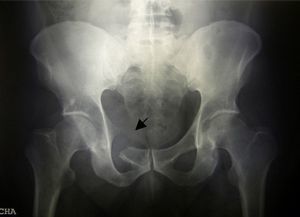

A 43-year-old male came to the clinic due to mechanical lower back pain, which had lasted for 2years. Physical examination showed painful limitation for right leg flexion and extension, with no neurological deficit. Laboratory analysis highlighted hemoglobin 10.6g/dl, normal ESR and GGT 111U/L (0–40). Simple X-ray (Fig. 1), CT (Fig. 2) and MR (Fig. 3) of the hips evidenced a 90mm×80mm×80mm mass in the right hemipelvis with an osteolytic component which affected half of the cotillus, iliac and pubic ramus, displacing the bladder and subjacent structures leftward.

X-ray findings reflect osteolysis, erosions, periostitis and soft tissue masses, as in our case. Immunohistochemistry is important to establish the differential diagnosis.5